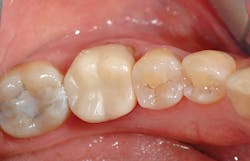

The final restoration is pictured in Figure 5.

Figure 5: The final Celtra Duo crown on tooth No. 19 after definitive cementation with Calibra Ceram and Prime&Bond Elect.